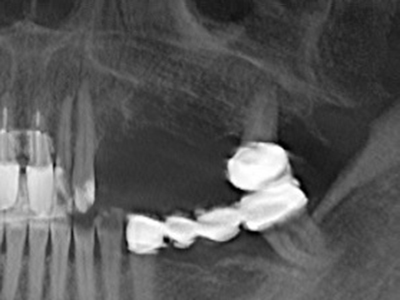

Fig. 17a: immagine TC di un'osteotomia con promozione di crescita immediatamente adiacente a...

Fig. 17b: dotto dell'alveolo dentale con irritazione del nervo (vista laterale e coronale).